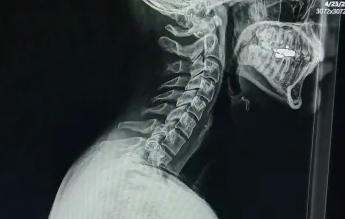

The neck pill. this is an xray of my neck

Look at this disgusting angle, it makes me lose about .5 of an inch ( this is a rough estimate )